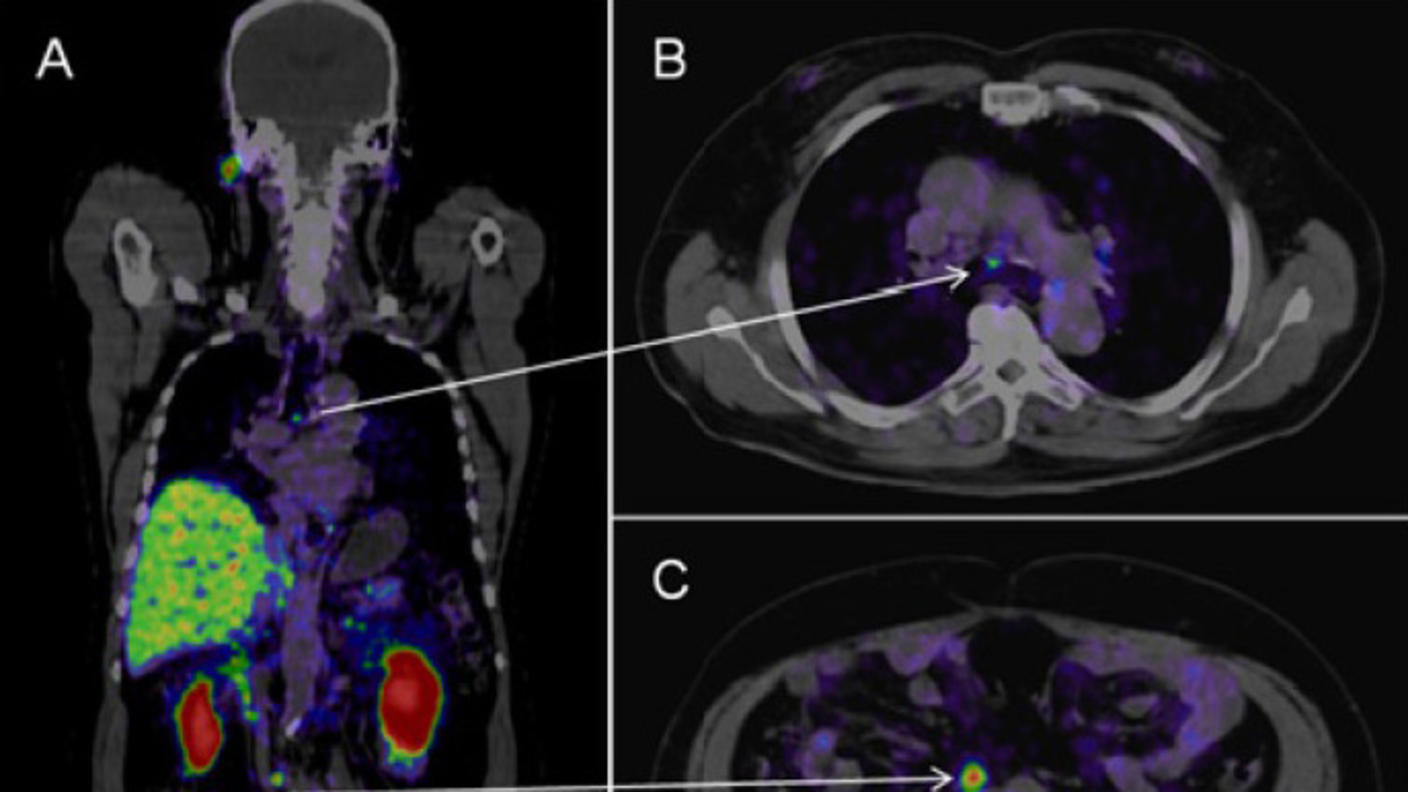

The next phase of the ongoing study will address that, Dr. Yamoah explained. Every year, participants with high genomic-risk cancer will get an imaging test, called a PSMA PET scan, to check if their tumors have spread beyond the prostate.